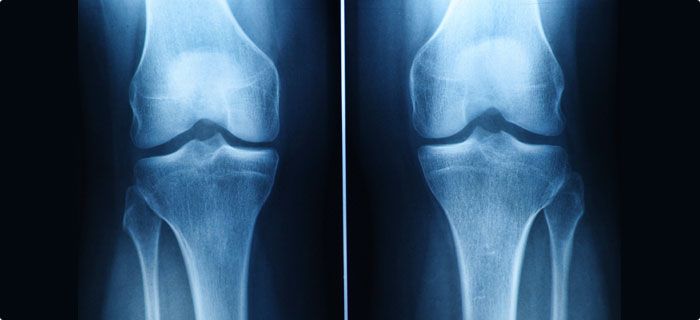

Швейцарские ученые использовали клетки, взятые из носа пациента, для получения хрящевой ткани. Созданные таким образом коленные хрящи были пересажены 10 взрослым в возрасте от 18 до 55 лет. Трансплантация была проведена еще два года назад, но об успехе операции ученые и врачи сообщили лишь сейчас, сообщает Медпортал.

Спустя два года после трансплантации у 9 пациентов из 10 отсутствовали какие-либо осложнения, связанные с пересадкой. Один из участников не смог пройти необходимые обследования, так как получил серьезную травму).

Читайте такжеУченые установили, что инъекции на основе пчелиного яда предотвращают разрушение хрящейПациенты отметили снижение болевых ощущений, улучшение работы коленного сустава, а также общее улучшение качества жизни. Несмотря на то, что процедура оказалась эффективной, о ее внедрении в клиническую практику говорить пока преждевременно – наблюдение за пациентами еще продолжается. Кроме того, нужно опробовать методику на большем количестве пациентов, а также сравнить эффективность такого лечения со стандартными методами терапии и плацебо.